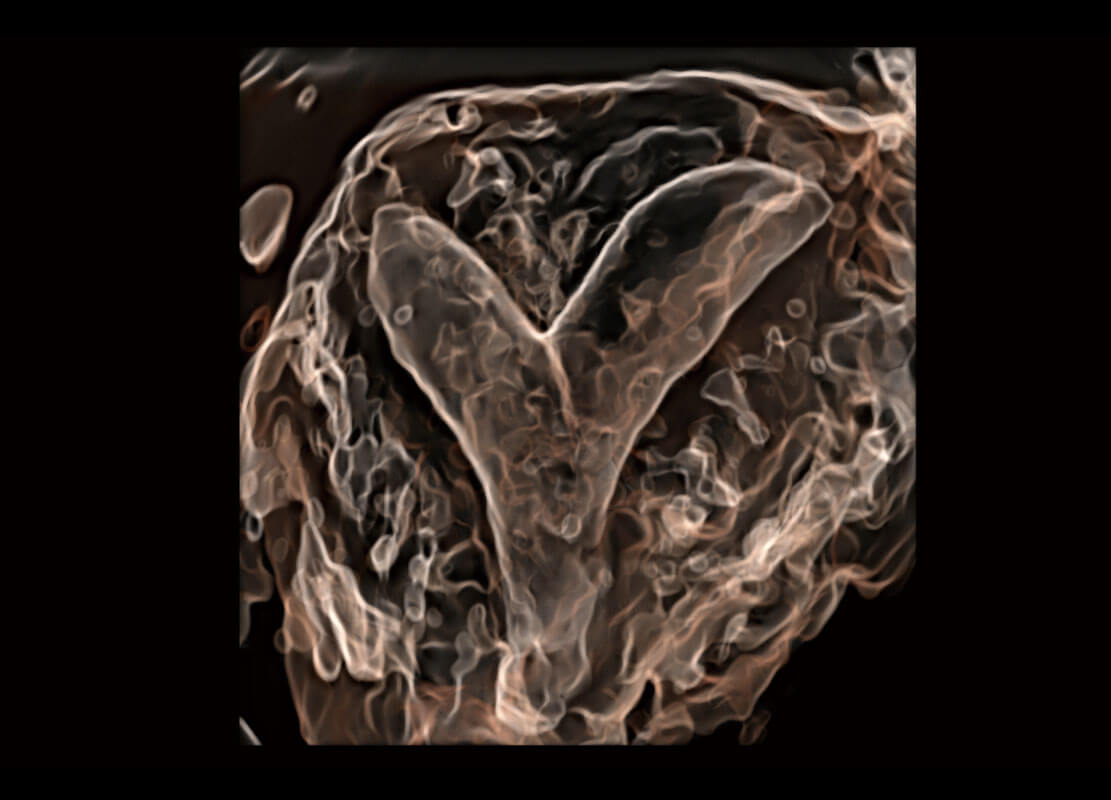

腔内三维-光影成像

右室双出口

胎心容积成像